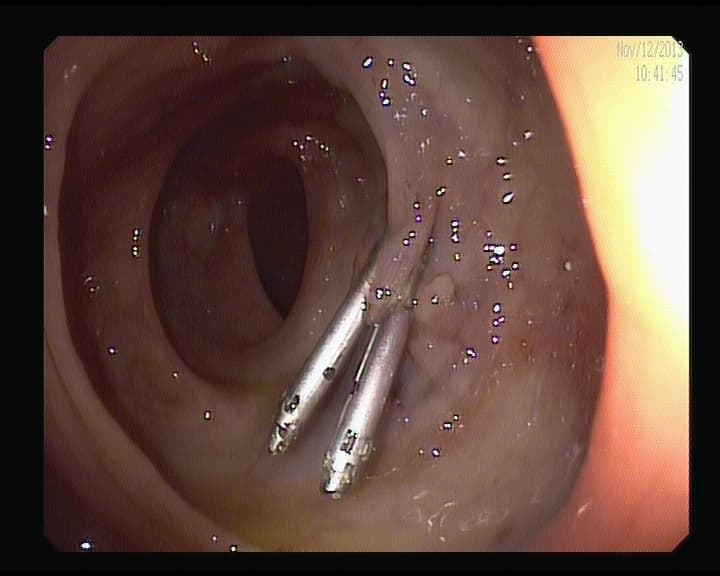

2clips Metálicos en colon.

2 clips metálicos colocados tras la resección endoscopica de un pólipo, aseguran ausencia de sangrado diferido.